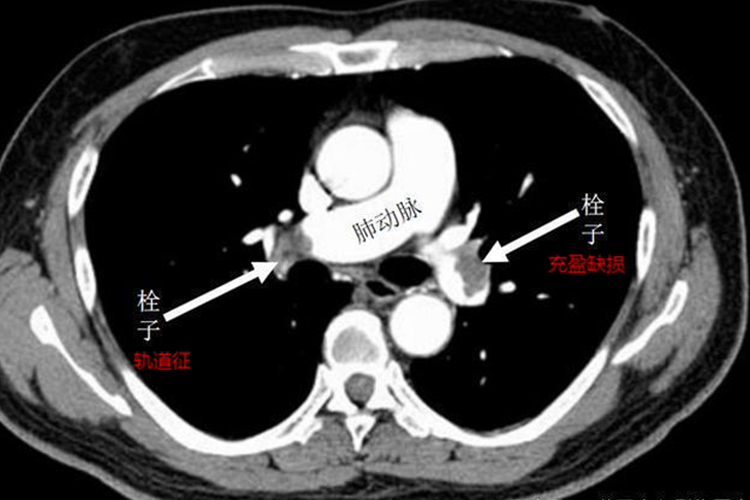

肺栓塞:一般无皮肤表面症状,主要出现呼吸困难、气促、胸痛等自觉症状,或者出现咯血、晕厥、发热等临床表现。

肺栓塞:在临床针对急性肺栓塞的处理原则是早期诊断,早期干预,根据病人的危险度分层选择合适的治疗方案和治疗疗程,包括严密监护呼吸、心率等变化,给予吸氧纠正低氧血症,同时给予抗凝、溶栓等治疗,必要时给予手术碎解、抽吸、摘除血栓。